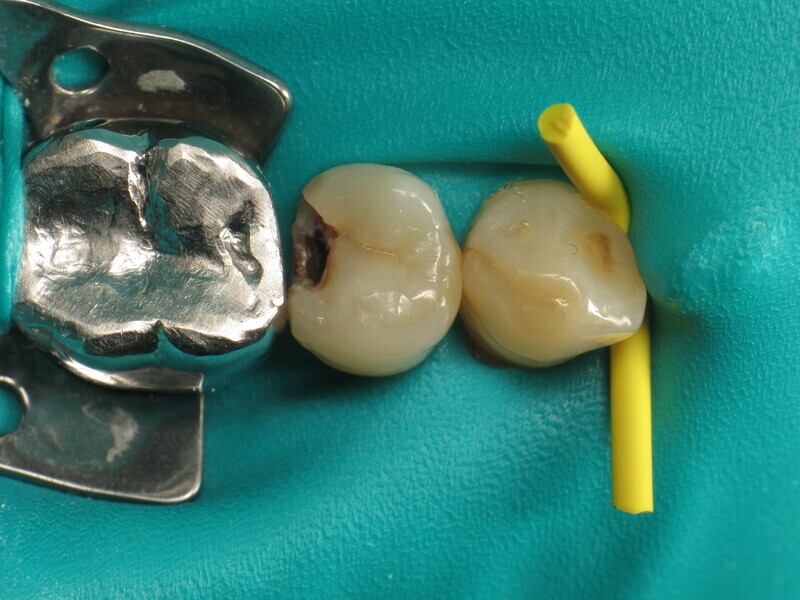

Le cas clinique décrit dans cet article porte sur une cavité de classe II sur une prémolaire (45) qui sera restaurée à l’aide d’un composite thermovisqueux (Fig. 1). La dent est isolée avec une digue en latex (Fig. 2). La cavité de classe II est ensuite nettoyée (Fig. 3). Afin d’obtenir une paroi distale anatomiquement correcte, une matrice, un coin et un anneau sont placés (Fig. 4). L’émail dentaire est ensuite mordancé pendant 30 secondes et la dentine pendant 15 secondes (Conditioner 36, Dentsply Sirona ; Fig. 5) puis rincé abondamment (Fig. 6). En raison de la faible épaisseur de dentine restante, une protection pulpaire (Telio Desensitizer, Ivoclar) est également appliquée (Fig. 7). L’adhésif (Futurabond DC, VOCO) est déposé dans la cavité pendant 20 secondes puis séché 5 secondes sous un jet d’air non gras et enfin, photopolymérisé pendant 10 secondes (Figs. 8 et 9). Pour un mouillage optimal, le fond de la cavité est recouvert d’un composite fluide extrêmement fin (GrandioSO Light Flow, A3.5, VOCO) et durci en 20 secondes (Figs. 10 et 11).